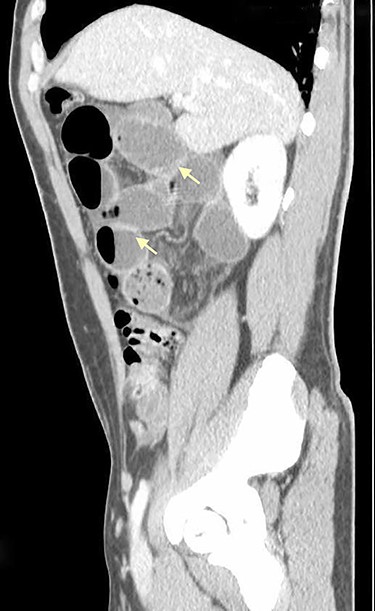

On physical examination, he was eupneic, hemodynamically stable and apyretic. His abdomen was soft, not distended, painless, with normal bowel sounds. Rectal examination showed an empty ampulla. Blood analysis revealed mild leukocytosis and little increase in C-reactive protein. Plain radiograph of the abdomen revealed dilated small bowel loops with air/fluid levels. Abdominal ultrasound revealed swollen intestinal loops on the right flank and interloop fluid. For further clarification, abdominal and pelvic computed tomography (CT) scan showed small bowel distension, air/fluid levels and free fluid (Fig. 1); signs of intestinal malrotation, with alteration of the normal topography of the duodenal arch (Fig. 2) and retrocecal position of terminal ileum (Fig. 3).

Sagittal CT scan shows small bowel distension with air/fluid levels (arrows).